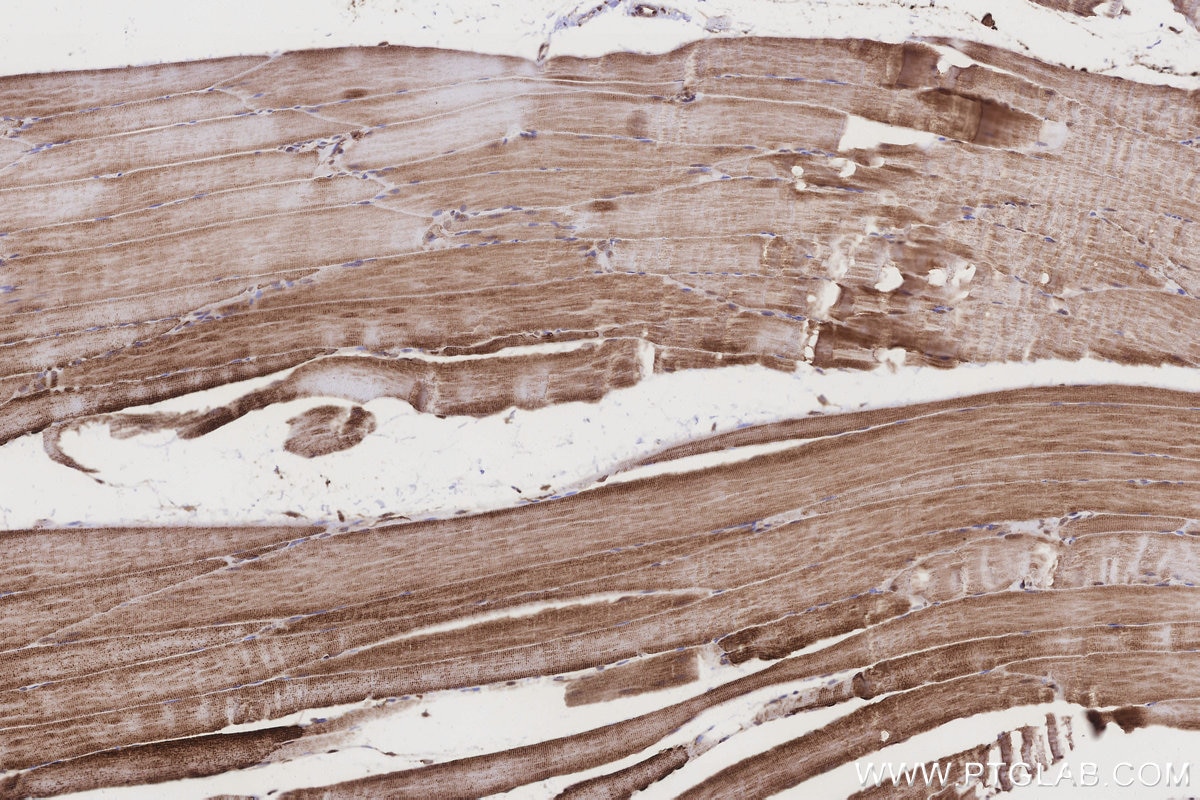

IHCeasy® CRAT Ready-To-Use IHC Kit

CRAT Ready-to-use reagent kit for IHC.

Validation Data Gallery

KHC3209 is a ready-to-use IHC kit for staining of CRAT. The kit provides all reagents, from antigen retrieval to cover slip mounting, that require little to no diluting or handling prior to use. Simply apply the reagents to your sample slide according to the protocol and you're steps away from obtaining high-quality IHC data.